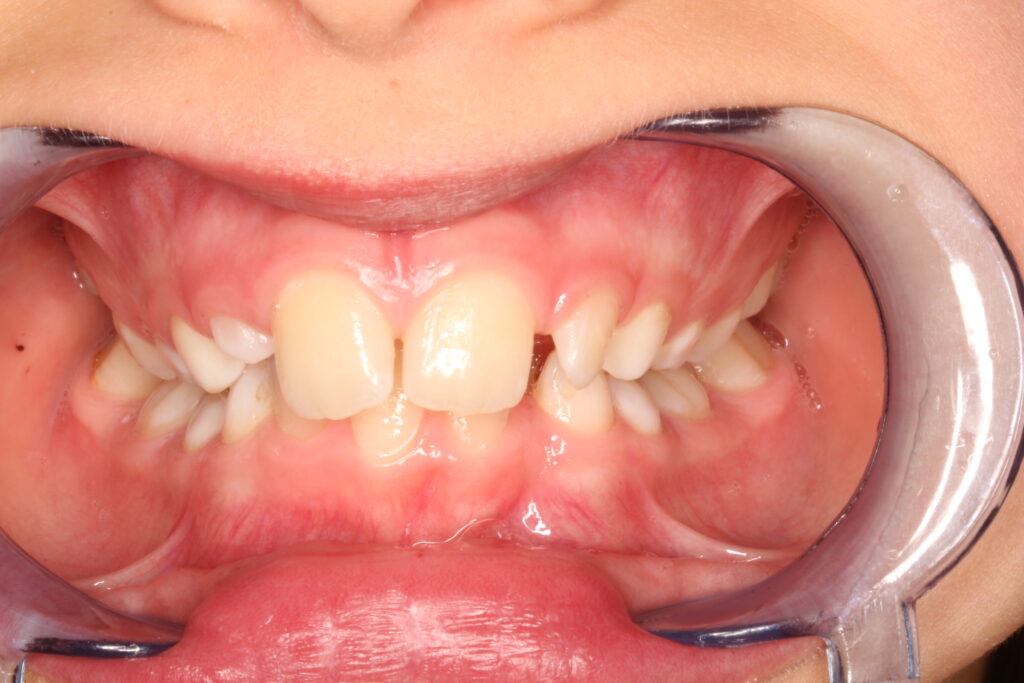

✔ Class II, Class III, aszimmetria és keresztharapás elméleti megközelítése

Az ALF készülék nem az agresszív erőhatásokra, hanem a funkcionális erők finom, biológiailag kíméletes irányítására épít. A klinikai tapasztalatok szerint ez tökéletes elég és mind a fogív fejlesztésében, keresztharapások megszűntetésében, helyteremtésben mind a nyelvtér növelésében jól működik.

A leggyakoribb a vegyes fogazat időszakában (6–11 év), de alkalmazható teljes tejfogazatban is nagyon korai kezelések esetében, akár 3-4 éves kortól is.